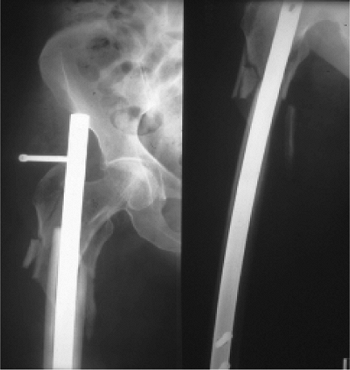

fall down stairs, sustained a Russell-Taylor IIB, closed,

subtrochanteric fracture (Fig. 20.47). She

underwent closed TriGen reconstruction nailing with a trochanteric

portal nail. Her fracture united, and she regained independent

ambulatory status by 4 months after surgery. This case represents the

advantages of a trochanteric portal with the MINIT in comminuted

fracture situations.

![]() |

Figure 20.47. A,B Russell Taylor IIB subtrochanteric fracture from a low-level fall. C,D. Reduction and stabilization with trochanteric antegrade TriGen nail in reconstruction mode with MINIT.